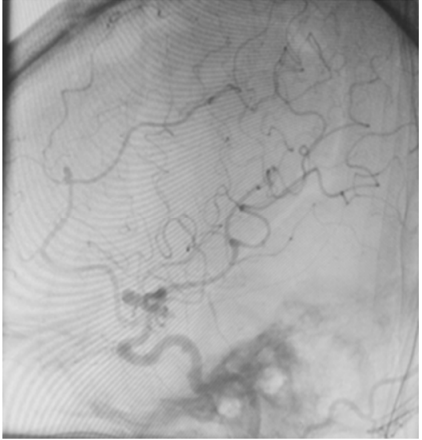

Uma paciente de 66 anos de idade, tabagista, hipertensa com tratamento irregular. Apresentou cefaleia súbita de severa intensidade associada a náuseas. Ao exame físico, observaramse AC = RR2T com BNF, FC = 100 bpm, AP = MVF sem RA, FR = 15 irpm, PA = 182 mmHg x 100 mmHg, SatO2 em ar ambiente = 97%, Glasgow 15, pupilas isofotorreagentes, sem deficits focais. TC crânio e arteriografia a seguir.

Fonte: Acervo pessoal.

Acerca desse caso clínico e com base nos conhecimentos médicos correlatos, julgue os itens a seguir.

O risco de ruptura transoperatória do aneurisma roto da paciente é maior em uma cirurgia tardia quando comparado com a cirurgia precoce.

Apenas um dos aneurismas evidenciados na angiografia pode ser acessado pelo acesso pterional.